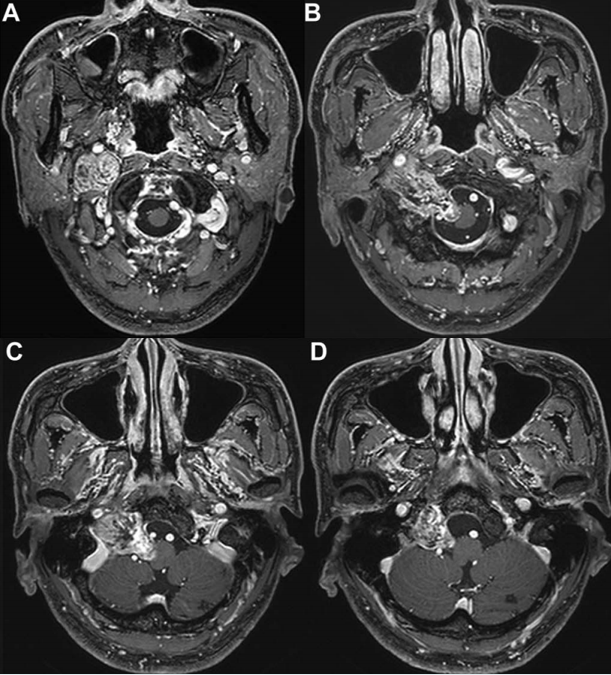

32岁男性患者李先生因持续性声音嘶哑伴饮水呛咳就诊。影像学检查发现颅内存在3.7厘米巨大肿瘤,伴囊性变,直接压迫颈内静脉并向颅底颈静脉孔区延伸。

术前MRI评估显示,考虑到肿瘤体积较大且内部出现囊性变,医疗团队认为手术切除比立体定向放疗更为适宜。手术关键环节在于精细分离肿瘤与周围重要神经血管结构,特别是后组颅神经和颈内动脉,必须避免损伤。

手术过程顺利,实现肿瘤全切,受压颈内静脉恢复正常血流。患者术后颅神经功能保留良好,仅出现短暂轻微不适后完全恢复。术后MRI复查证实肿瘤完全切除,未出现新发神经功能损伤。